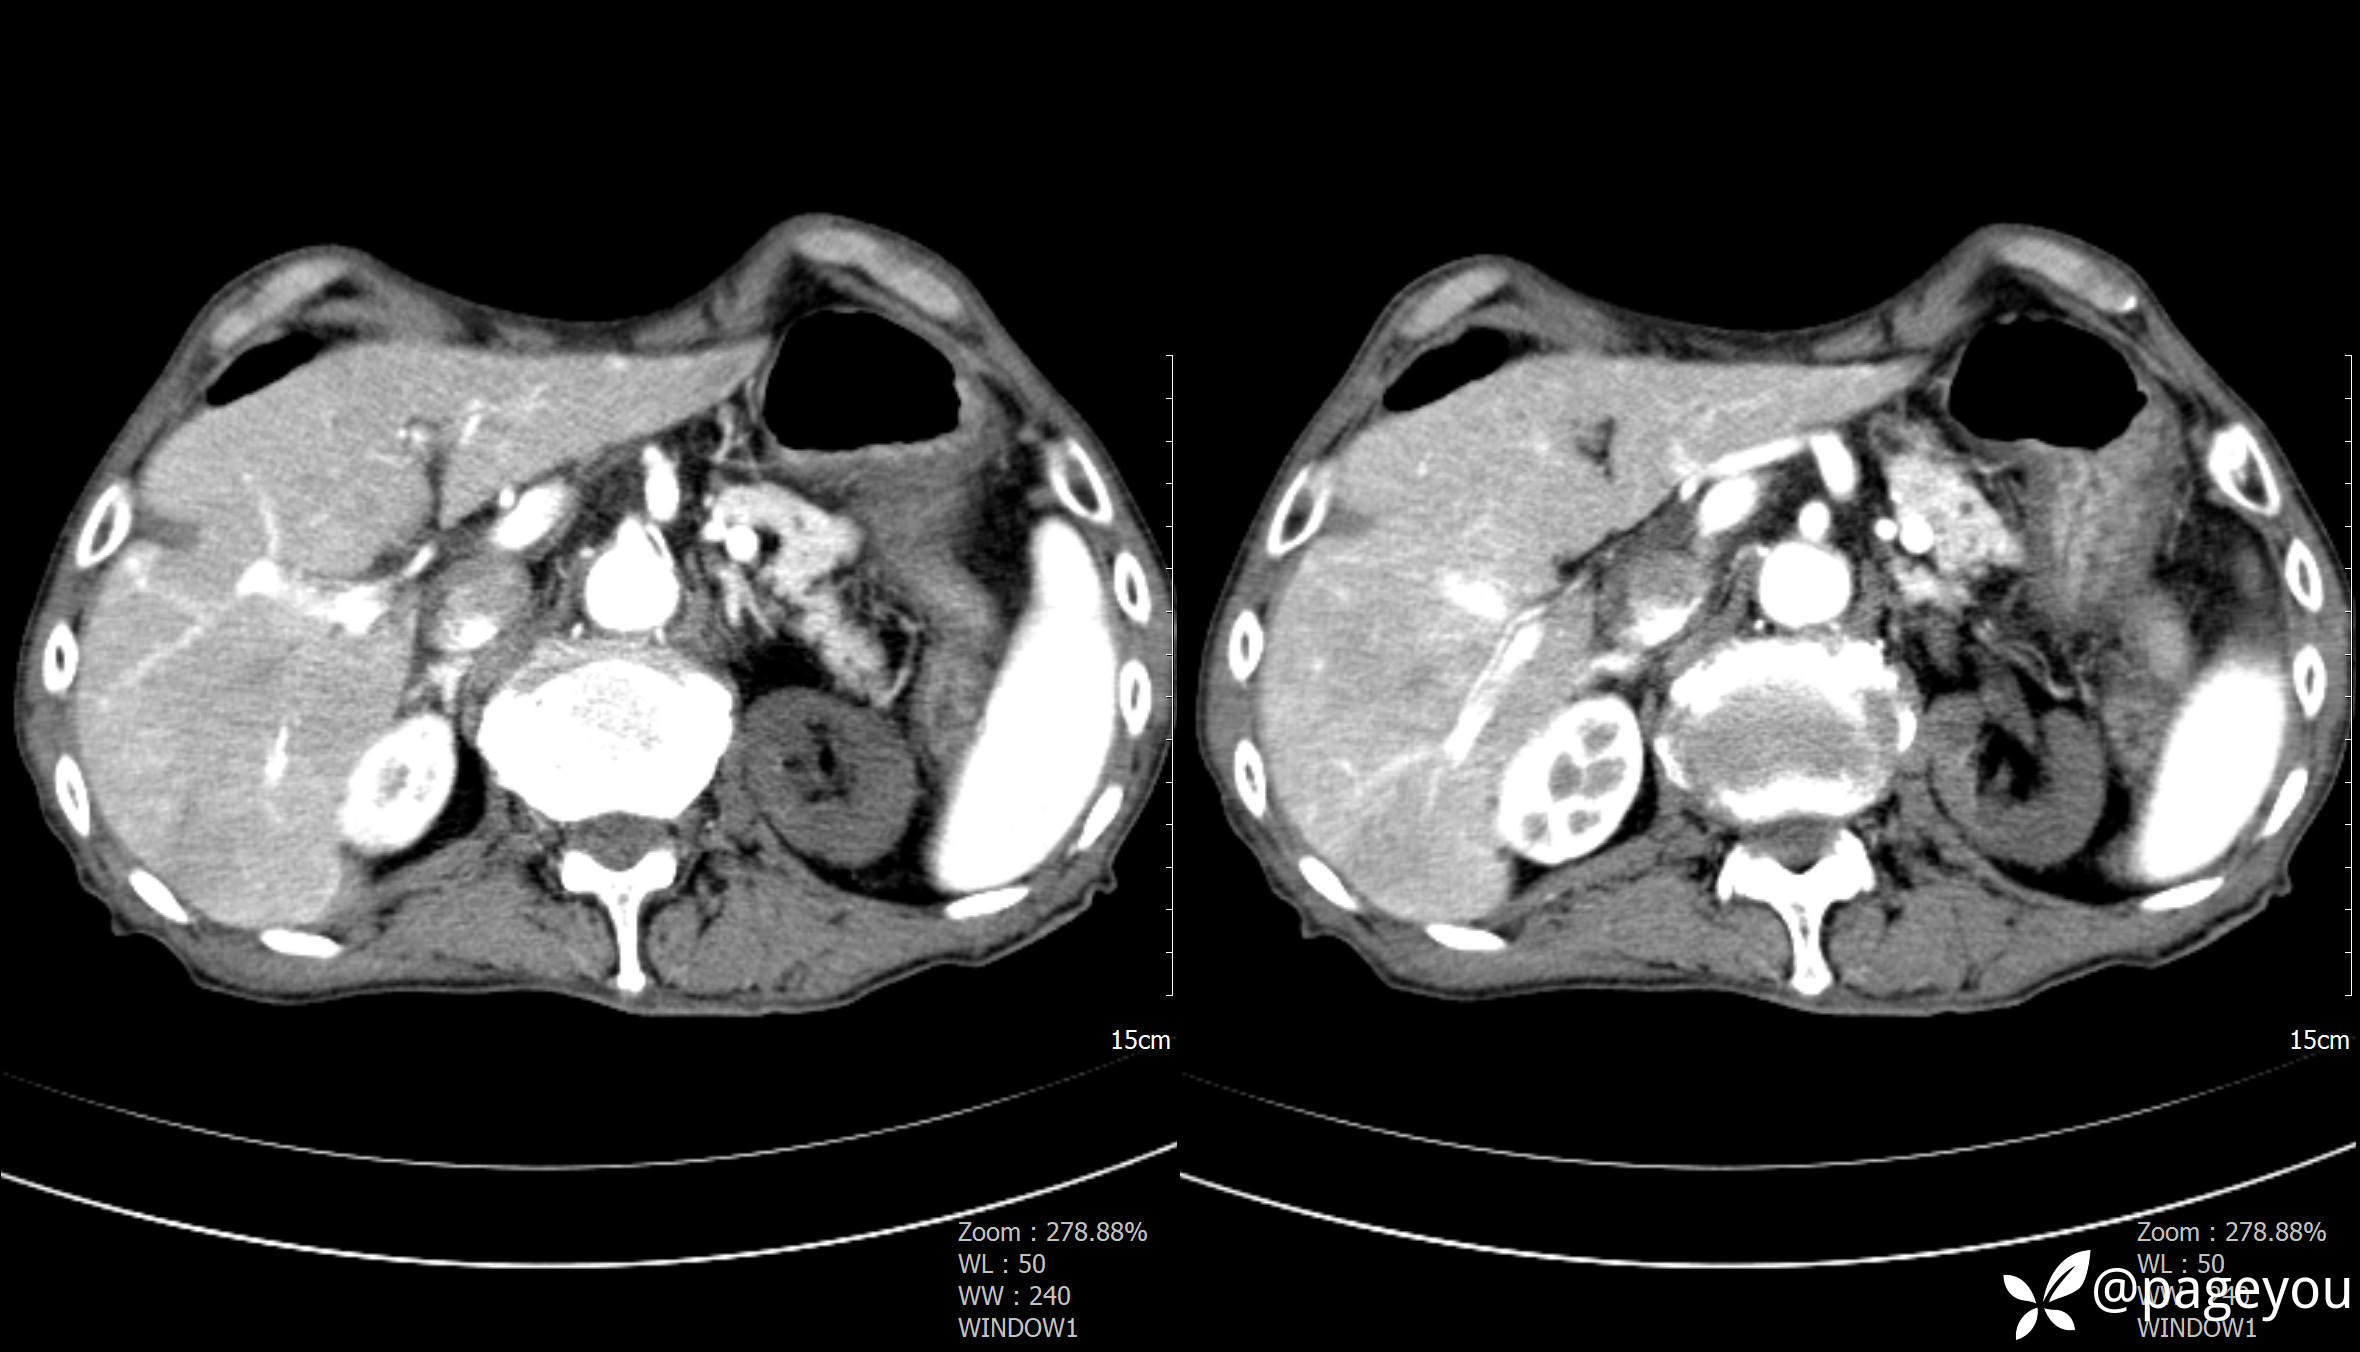

主动脉CTA: